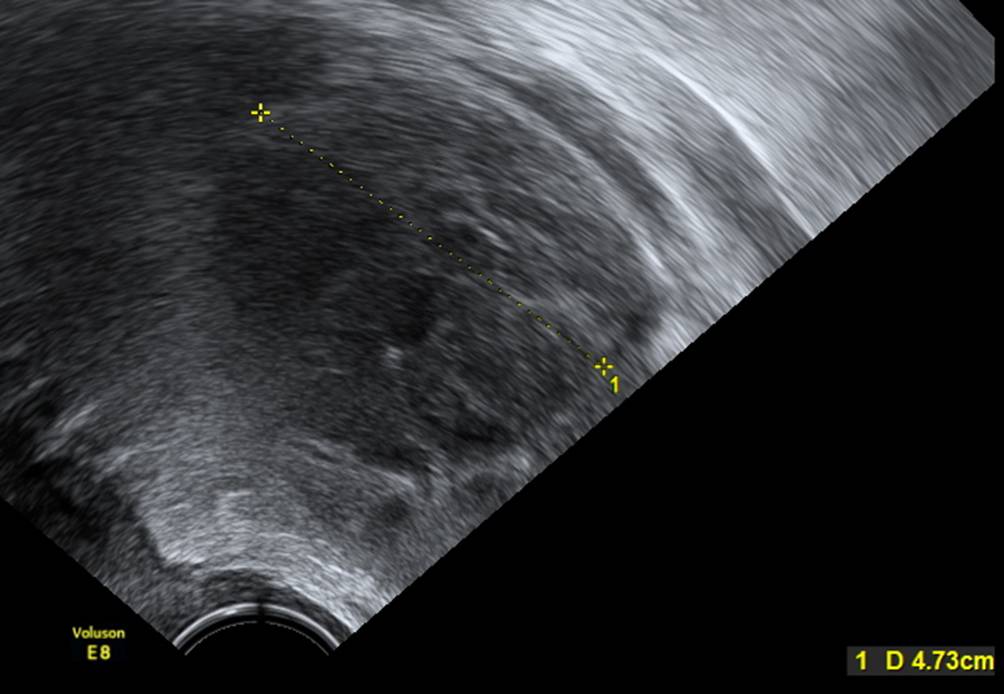

Abb. 8

Beispiel für Aszites: Dieser Befund muss in der ADNEX-Fragenliste mit „yes“ angegeben werden und führt zu einer Erhöhung des kalkulierten Risikos